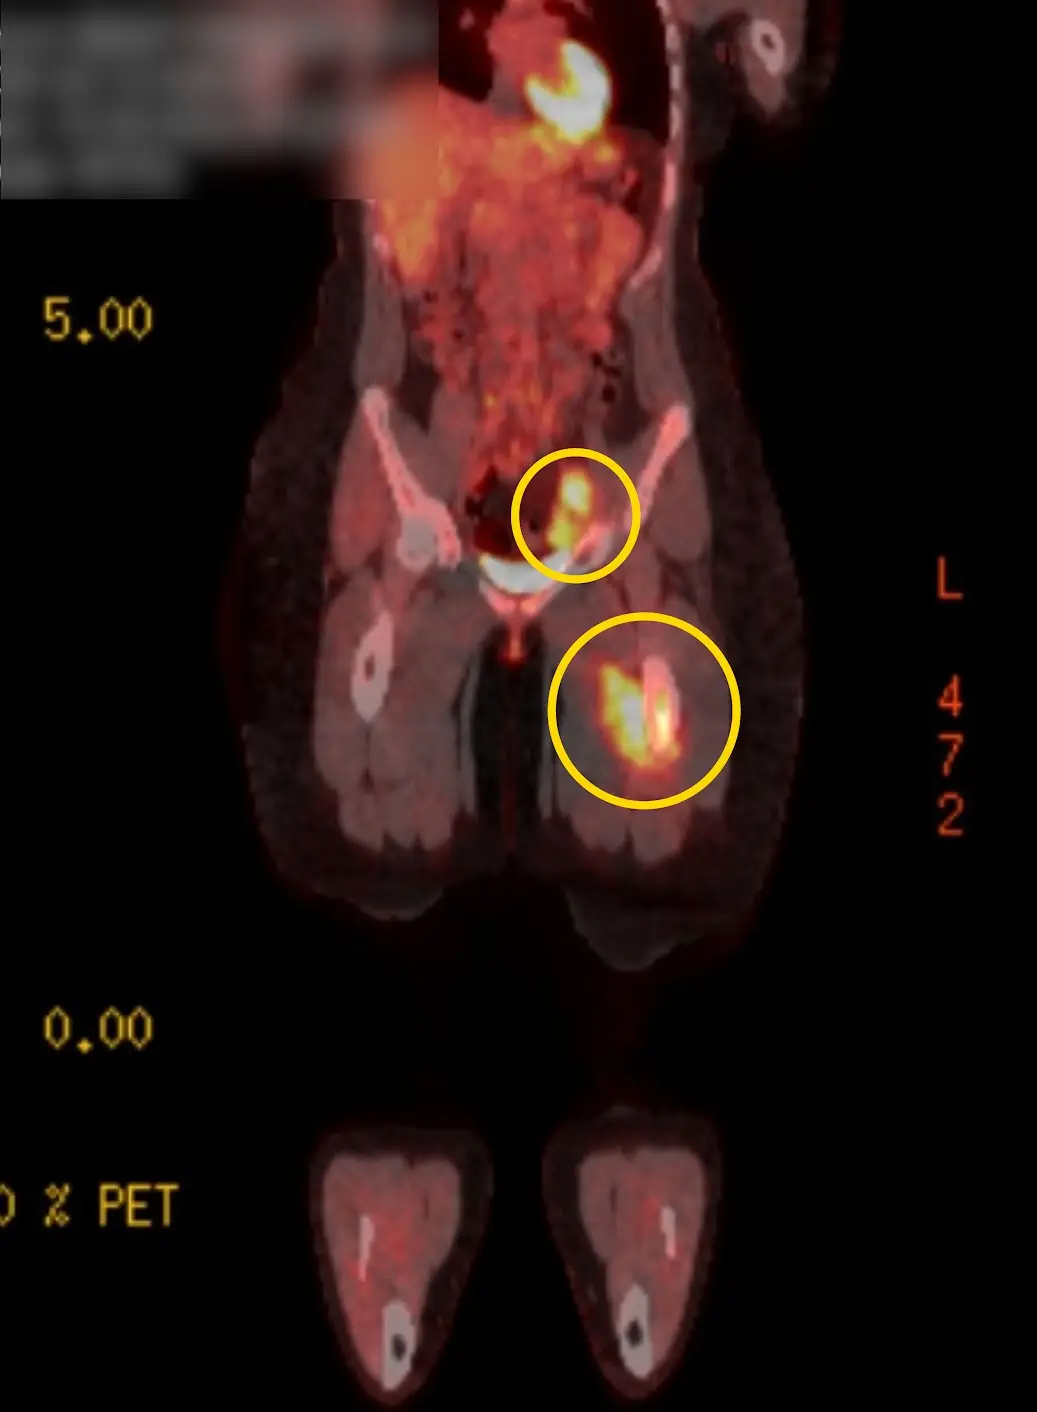

After the scans, it was revealed that Bailey actually had two tumors, one in her femur and one in her groin, and she was diagnosed with stage four Ewing sarcoma, a type of soft tissue cancer.